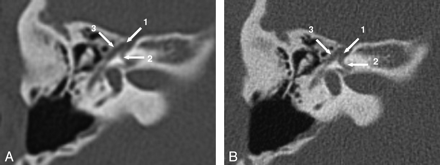

Facial nerve canal axial MPR, section thickness 0.8 mm, in both SST (A) and MSCT (B). The geniculate ganglion (1), labyrinthine segment (2), and the tympanic segment (3) of the facial nerve can be seen in diagnostic quality with both imaging techniques. Note the status postmastoidectomy.